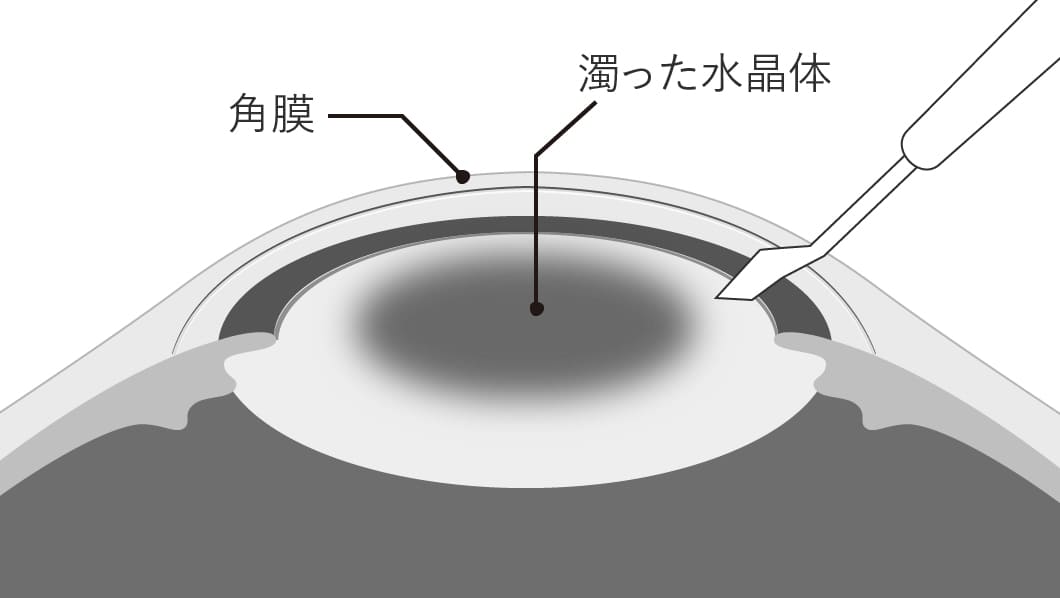

濁った水晶体が元に戻ることはありません。

そのため、手術で水晶体を取り除き、代わりに「眼内レンズ」という人工のレンズを挿入し、見え方を改善します。

- 1切開します。

-